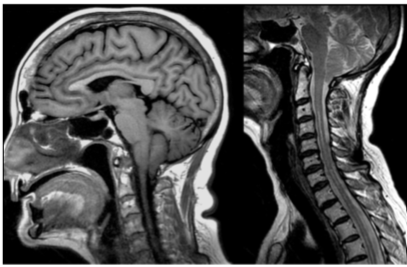

Paciente do sexo feminino, de 63 anos, realiza estudo por ressonância magnética para avaliação de cefaleia, sendo diagnosticado malformação de Chiari tipo I.

A respeito das características da malformação de Chiari tipo I tem-se que: